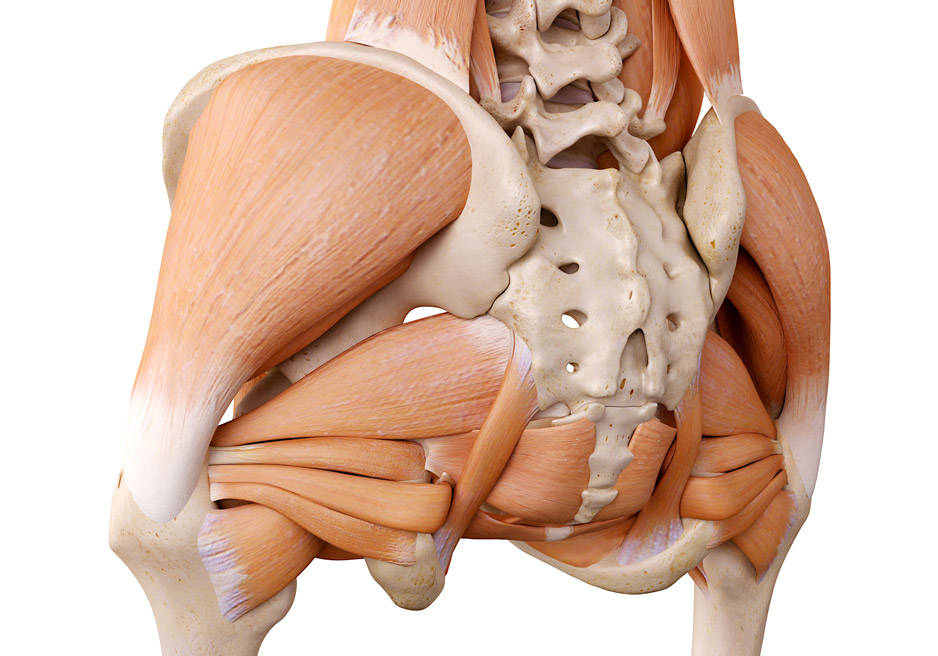

Анатомия мышц: Пириформис